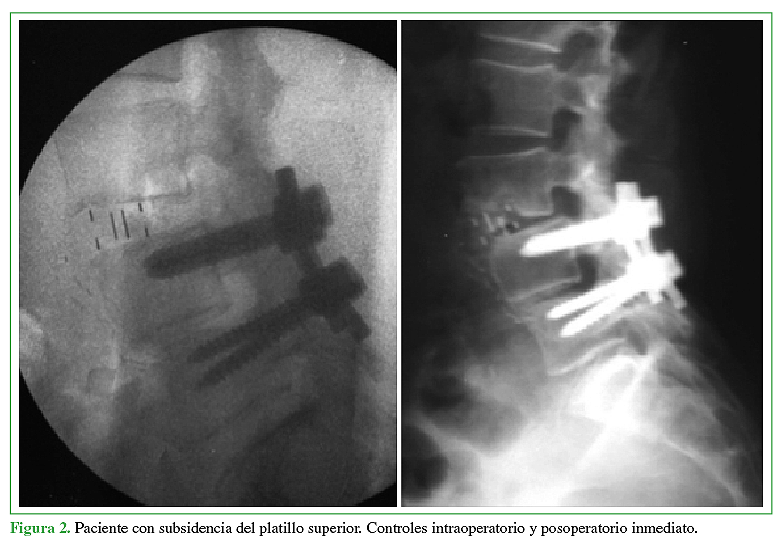

Complicaciones tempranas en los primeros 50 casos de cirugía mínimamente invasiva lateral a la columna lumbar

Acceso mediante suscripción PDF Acceso mediante suscripción PDF_EN (English) Acceso mediante suscripción Figura 1 Acceso mediante suscripción Figura 2 Acceso mediante suscripción Figura 3 Acceso mediante suscripción Tabla 1 Acceso mediante suscripción Tabla 2 Acceso mediante suscripción Tabla 3 Acceso mediante suscripción Tabla 4 Acceso mediante suscripción Tabla 5 Acceso mediante suscripción HTML -